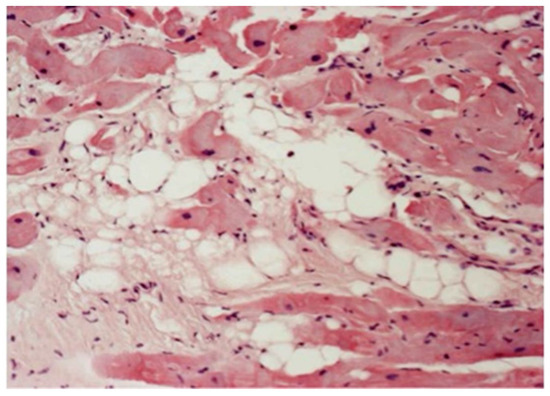

4. Pathological Substrates